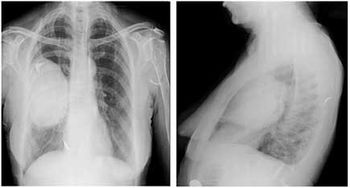

Case History: 65-year-old woman with dry cough, sore throat and mild fever, had upper airway infection diagnosis and similar attacks in previous years.

Published: February 3rd 2015 | Updated: